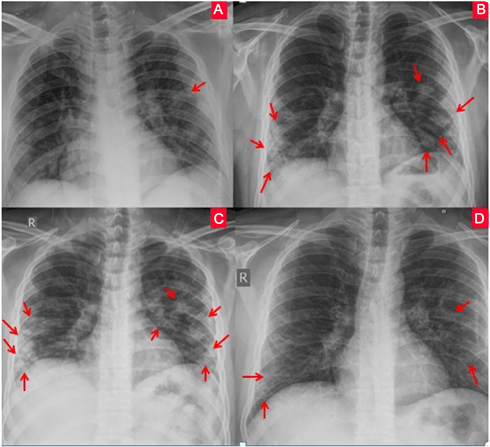

Covid Normal Man Chest X Ray Fresco

Destacados What Are The Common Radiographic Findings Of Coronavirus Disease 2019 Covid 19